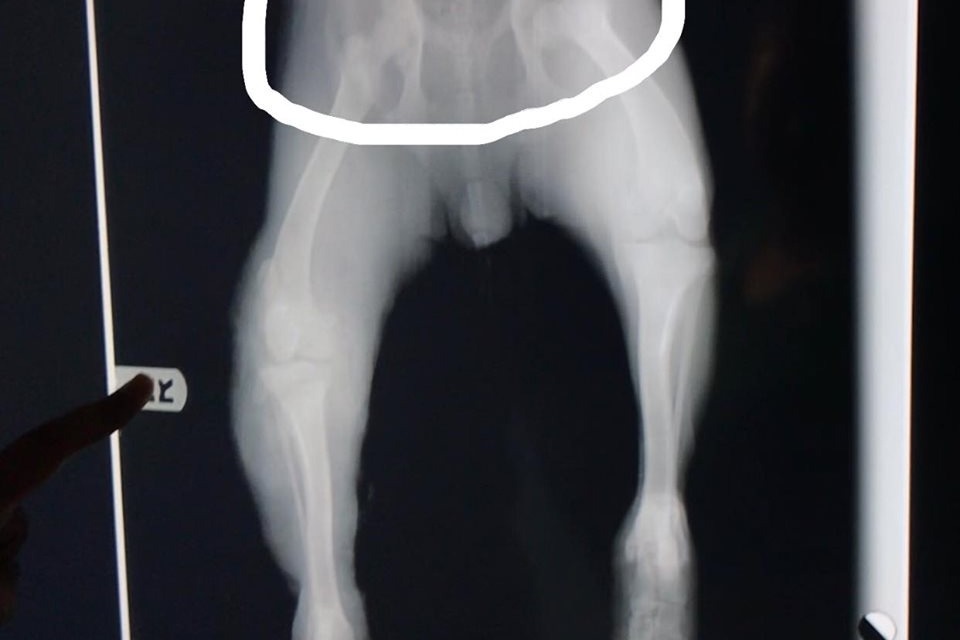

The dog was hit by a car and sustained some serious injuries to her legs. The young lady’s name is Sarai. She named the dog Merida. Sarai took Merida to the vet in San Felipe, but after they told her that they will have to amputate both Merida’s legs, she drove all the way to Mexicali to see another vet. The vet in Mexicali said that Merida will need three surgeries, and they are certain they can save her legs.

The open wounds on Merida’s legs need to heal first, before the surgery can be performed. Sarai has been driving Merida to Mexicali weekly to check on the progress and change the bandages. Each appointment and a bandage change costs $800 pesos (about $45 US dollars). She also has to pay for the gas.